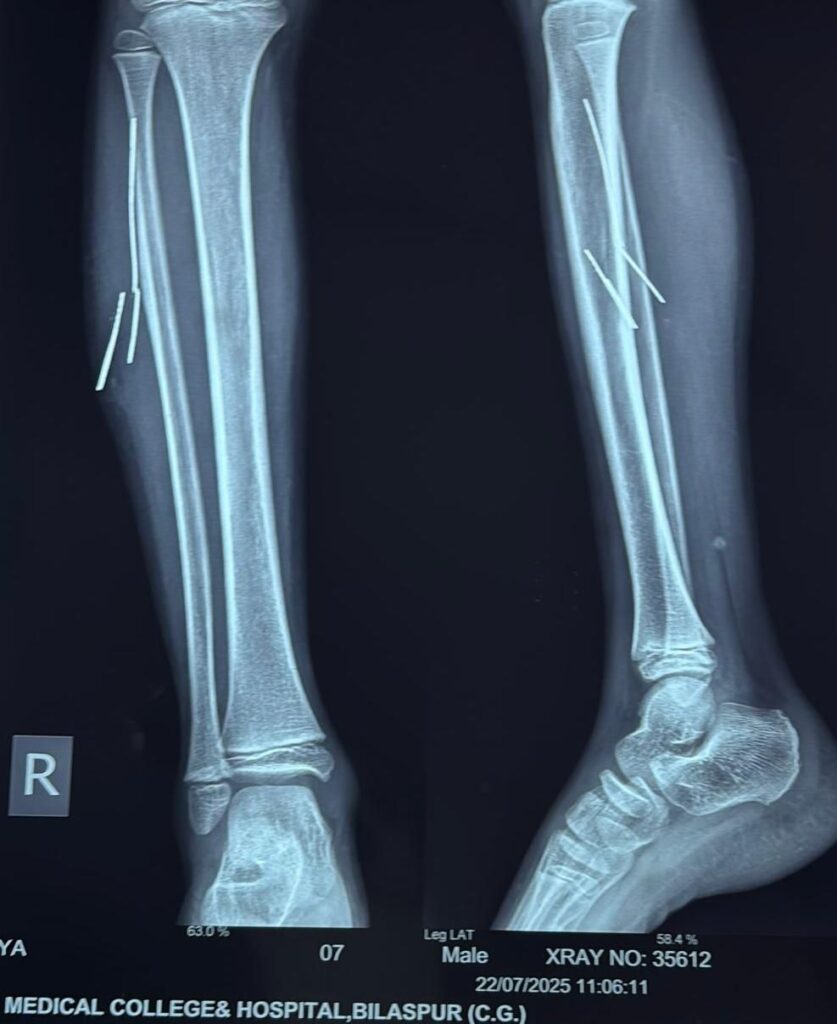

सर्जरी विभाग के वरिष्ठ सर्जन डॉ. बी.डी. तिवारी ने स्थिति की गंभीरता को देखते हुए एक्स-रे और सोनोग्राफी की जांच करवाई। जाँच में यह स्पष्ट हुआ कि चार लोहे के टुकड़े 2 से 5 सेमी की लंबाई में मांसपेशियों में धंसे हुए हैं और संक्रमण की आशंका भी बढ़ चुकी है।

ऑपरेशन का निर्णय लिया गया, लेकिन जटिलता को देखते हुए ऑपरेशन के दौरान रेडियोलॉजी विभाग की मदद ली गई। विभागाध्यक्ष डॉ. अर्चना सिंह के मार्गदर्शन में असिस्टेंट प्रोफेसर डॉ. अमन अग्रवाल ने ऑपरेशन थिएटर में ही लाइव सोनोग्राफी कर तारों की सटीक स्थिति को चिन्हित किया।